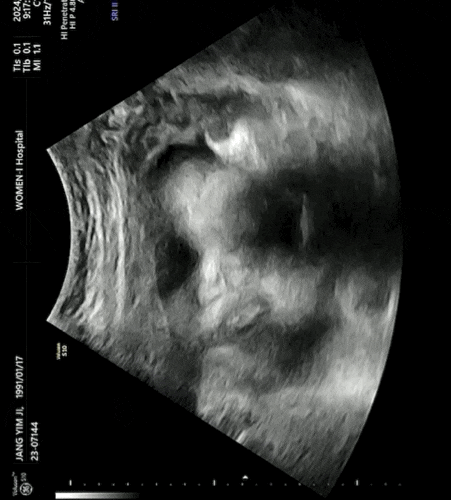

임신기록/ 36주차 증상 및 초음파 기록

36주차 증상 - 두 손 모두 많이 부어 거의 구부려지지가 않고 손목 통증이 엄청나게 심해진다( 안에서 칼로...

임신기록/34주차 증상 및 초음파 사진

34주차 증상 - 밤에 적게는 1번 많으면 3번정도 깨서 화장실을 간다 - 이 시기때쯤 태동이 준다고 했지만 ...